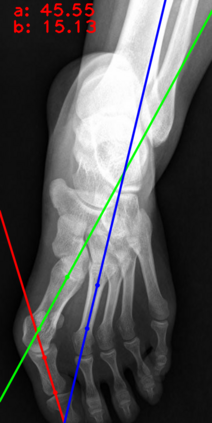

Angular measurements is essential to make a resonable treatment for Hallux valgus (HV), a common forefoot deformity. However, it still depends on manual labeling and measurement, which is time-consuming and sometimes unreliable. Automating this process is a thing of concern. However, it lack of dataset and the keypoints based method which made a great success in pose estimation is not suitable for this field.To solve the problems, we made a dataset and developed an algorithm based on deep learning and linear regression. It shows great fitting ability to the ground truth.